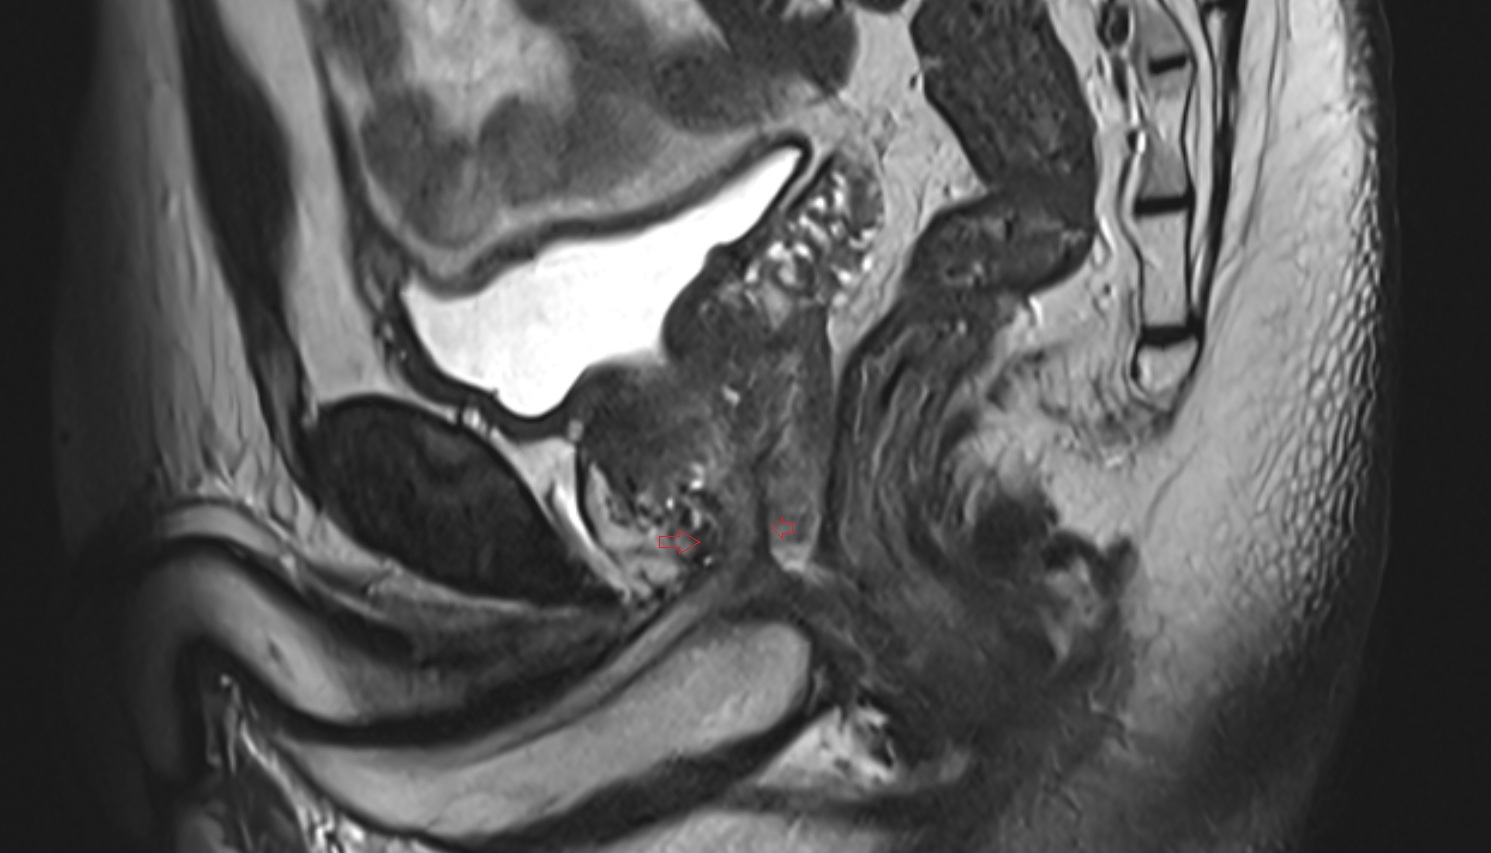

- Uterus

- Body of uterus

- Fundus of uterus

- Cervix of uterus

- Isthmus of uterus

- Vagina

- Fornix of the vagina

- Endometrium of uterus

- Myometrium of uterus

- Perimetrium of uterus

- Junctional zone of uterus